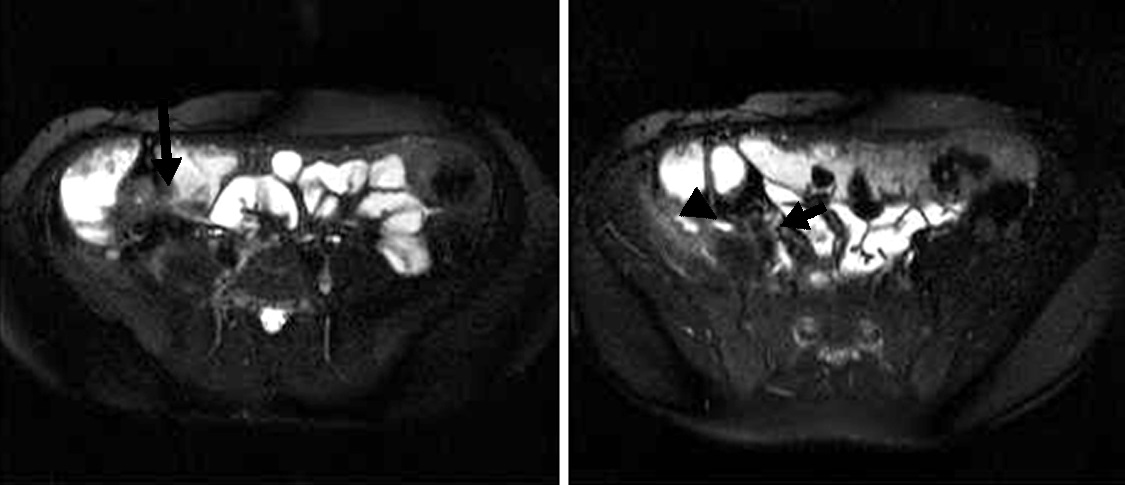

Figura 3

Enfermedad de Crohn a) Secuencia T2 axial sin supresión grasa evidencia engrosamiento parietal de la última asa ileal (flecha blanca).

b y c) secuencias T1 con saturación grasa y gadolinio. Realce estrajpgicado dado por realce de la mucosa (flecha larga) y serosa (flecha corta) separadas por la capa submucosa edematosa (asterisco).